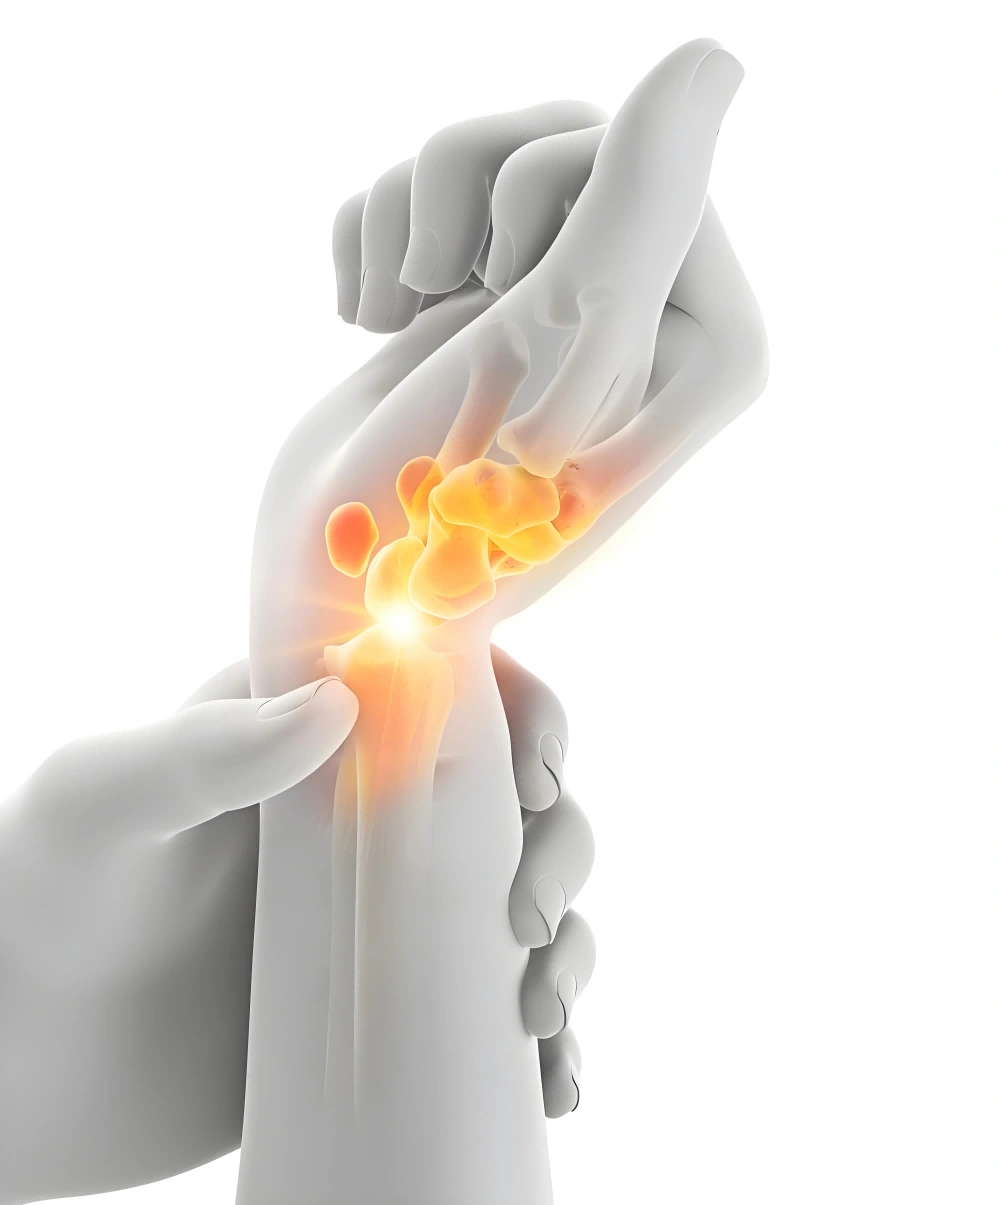

Moxibustion Notes: Natural Therapy For Arthritis Pain

Traditional Chinese Medicine (TCM) associates arthritis with “obstruction by cold and dampness” and “impaired qi and blood circulation”. Moxibustion uses the warmth of heat and the energy of herbs to dispel cold dampness and promote local qi and blood circulation, thereby relieving pain and restoring joint function. It is a gentle yet deep natural therapy…